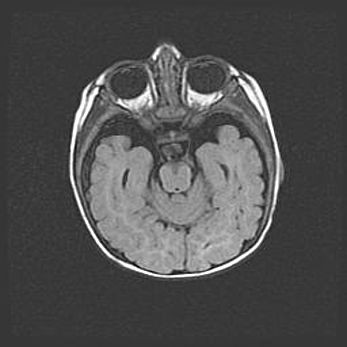

Ниже представлена  галерея МРТ снимков, полученных с применением LMT неонатальных матричных РЧ катушек. Также каждая группа МРТ снимков сопровождается информацией о пациенте (диагноз, возраст, вес, пол, срок гестации) и краткой сопроводительной расшифровкой диагноза.

Сообщающаяся гидроцефалия. Кистозная энцефаломаляция головного мозга.

Возраст: 3 месяца 4 дня

Вес: 3100 г

Пол: женский

Окружность головы: 34 см

Срок гестации: 31 неделя

Кистозная энцефаломаляция головного мозга - одна из форм поражения головного мозга в детском возрасте. Характеризуется возникновением множественных и распространённых кист в коре, белом веществе и подкорковых образованиях головного мозга у плодов, новорождённых и детей раннего возраста. Развитие кистозной энцефаломаляции связано с внутриутробной асфиксией и гипотонией, родовой травмой, тромбозом синусов, пороками развития сосудов, инфекциями, сепсисом и другими причинами. Наиболее значимые инфекционные агенты: вирусы простого герпеса, цитомегалии, краснухи, токсоплазмы, энтеробактерии, золотистый стафилококк и другие.